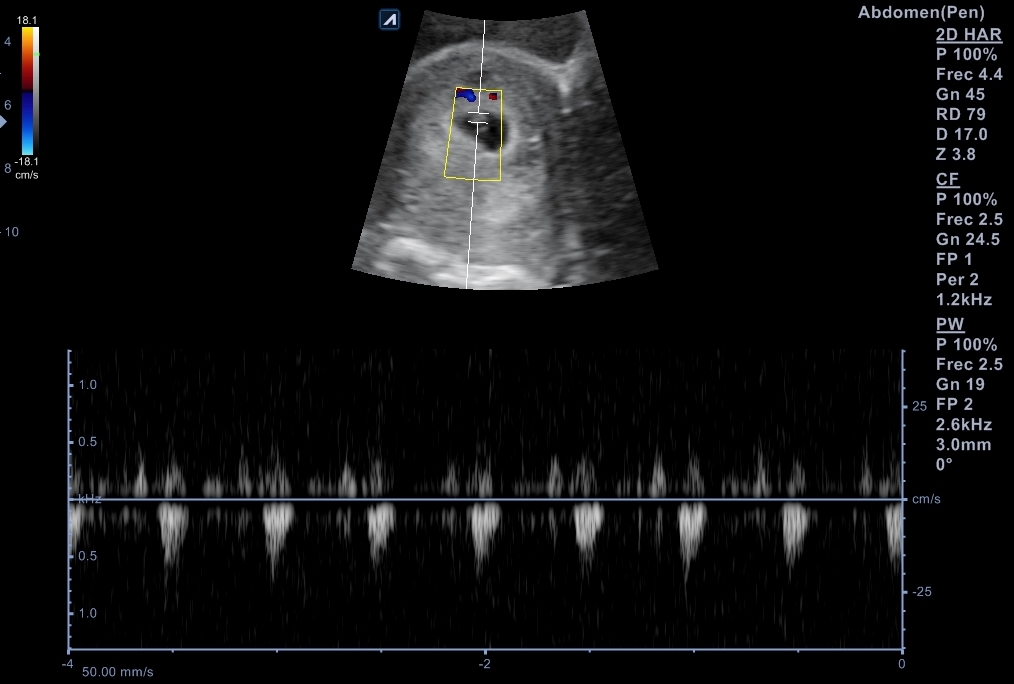

Nueva ecografía: saco embrionario con embrión con latido fetal a 135 lpm y se data de 6 + 4 semanas. Se cita para analítica de primer trimestre, así como con Obstetricia.